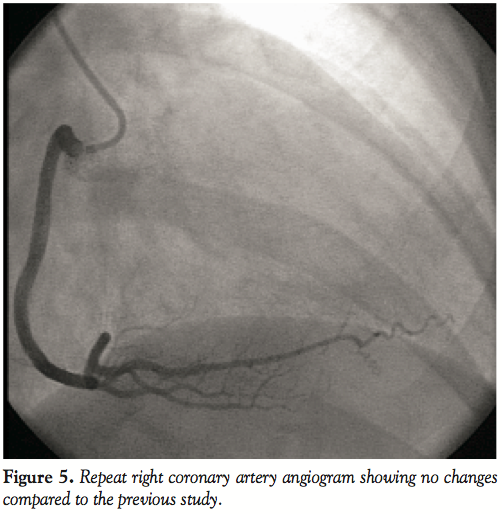

Three hours after the initial procedure, the patient went into cardiac arrest due to ventricular fibrillation. Post-arrest electrocardiogram showed ST-segment elevation in both the precordial and inferior leads (Figure 4). Emergency repeat coronary angiography was performed. Left coronary angiogram was normal and RCA angiogram showed no evidence of residual dissection with TIMI 3 flow, but the 3 marginal branches remained occluded (Figure 5).